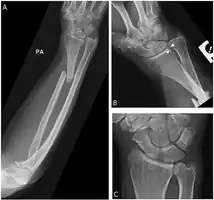

Galeazzi fracture

| Galeazzi fracture-dislocation | |

| Galeazzi fracture. Arrow points at the dislocated ulnar head | |

The Galeazzi fracture is a fracture of the distal third of the radius with dislocation of the distal radioulnar joint. It classically involves an isolated fracture of the junction of the distal third and middle third of the radius with associated subluxation or dislocation of the distal radio-ulnar joint; the injury disrupts the forearm axis joint.[1]